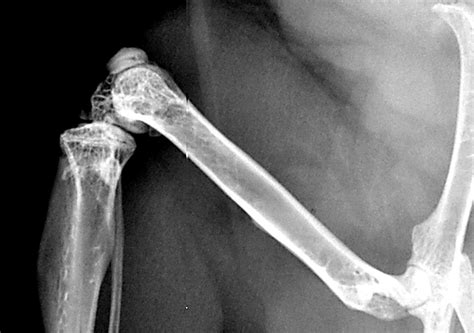

Arm Fractures

Arm fractures, including those of the humerus, radius, and ulna, are common injuries, especially in children and athletes. Treatment options include:

• Immobilization with a cast or splint.

• Surgery for severe fractures, such as open or comminuted fractures.

• Physical therapy to restore range of motion and strength.